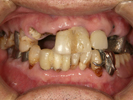

40代女性

奥歯が欠落して、全く噛めないと大変お困りの状態でした。

治療に1年半程要しましたが、熱心に通院してくださいました。

魚介類・お肉なんでも噛めるようになり、今ではニコッと笑える日々で楽しいですと、

アンケートにも答えてくださいました。

![]() |

| 治療前 | ||

| 治療後 | ||